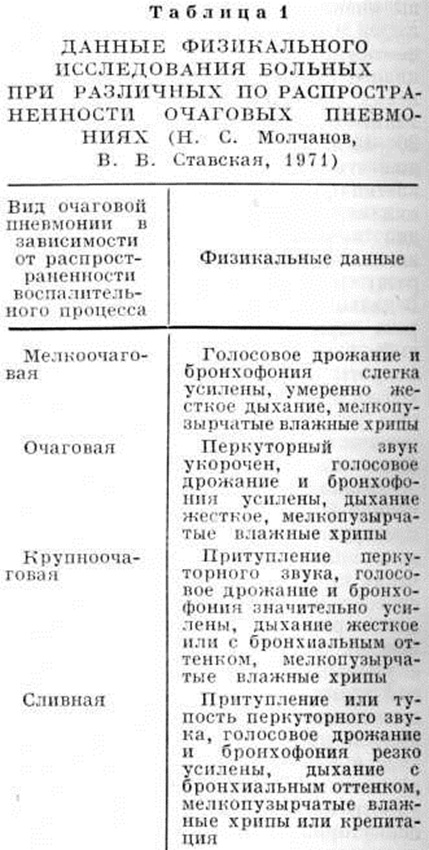

Физикальные данные при очаговых Пневмония отличаются большой вариабельностью и зависят от расположения (поверхностного или глубокого) и распространённости воспалительного процесса (таблица 1). Очаги небольших размеров, расположенные центрально или поверхностно, не сопровождаются изменениями голосового дрожания и перкуторного звука. Независимо от величины очагов при наличии бронхита или сопутствующего плеврита могут выслушиваться сухие хрипы и шум трения плевры.